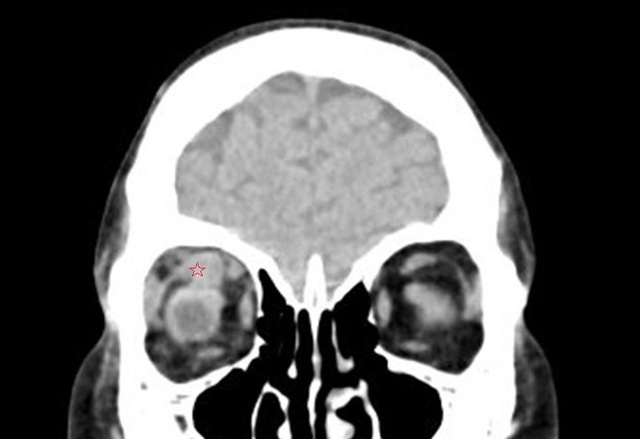

图 3 为平扫 CT,可见上直肌明显增粗(五角星)